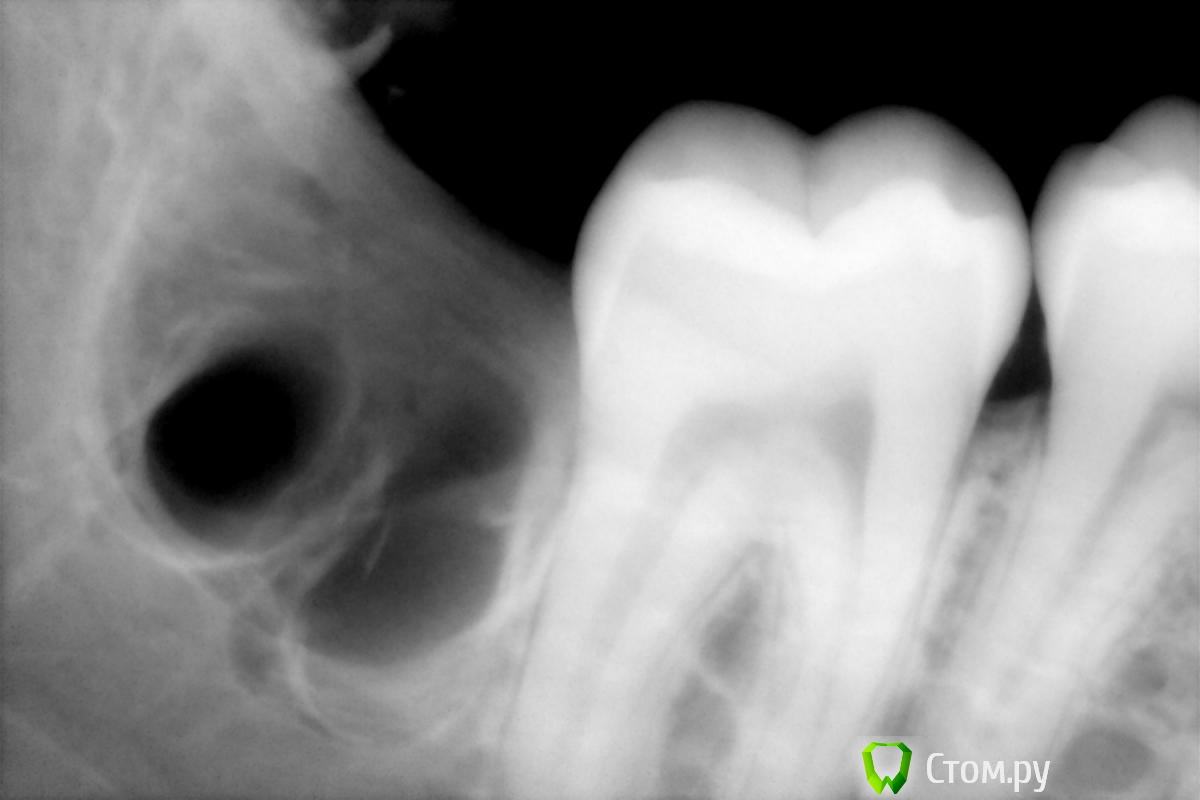

faity Опубликовано 30 июля, 2014 Поделиться Опубликовано 30 июля, 2014 (изменено) смотрим 4.8это после к сожалению в процессе удаления остались только мелкие фрагменты, не хотелось мягкие ткани сильно распахивать дистальный корень 90 градусов, медиальный 130-150 Изменено 30 июля, 2014 пользователем faity 4 Ссылка на комментарий